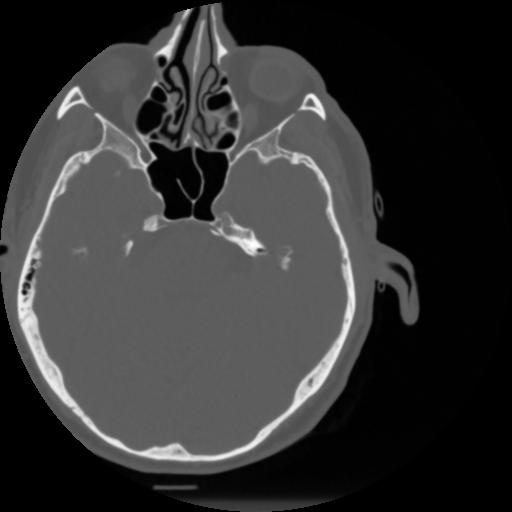

4 CEREBRO,,Vol,0.5,CEREBRO,,